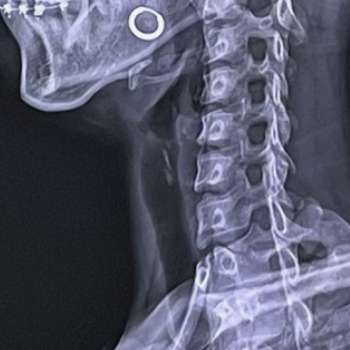

목디스크(경추 추간판 탈출증)는 목의 추간판이 탈출하거나 파열되어 주변 신경을 압박하는 질환입니다. 이로 인해 다양한 증상이 나타날 수 있으며, 각각의 증상은 환자에게 심각한 불편을 초래할 수 있습니다. 아래는 전문가적 입장에서 목디스크의 주요 증상 10가지를 상세히 설명하겠습니다.

이러한 증상들은 목디스크로 인한 신경 압박과 염증으로 인해 발생하며, 각 증상은 환자의 상태와 디스크 탈출 정도에 따라 다르게 나타날 수 있습니다. 환자는 이러한 증상을 경험할 때 조기에 적절한 진단과 관리를 받아야 합니다. 목디스크의 증상은 일상생활에 큰 지장을 줄 수 있으며, 조기 치료와 관리는 증상 완화와 생활의 질 향상에 도움이 될 수 있습니다.